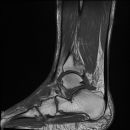

Totale Talusluxation

Talus Fraktur

Snowboard fracture Talus